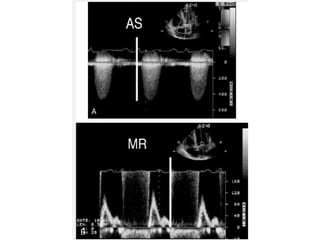

 Mistaken identity of the recorded signal

 Mitral regurgitation jet has a contour similar to that of the jet of

severe aortic stenosis. because of similarities in location and

direction of the two jets, mistaken identity can occur.

Can be avoided by

 1.Two jets should be recorded by sweeping the transducer back

and forth to clearly indicate to the interpreter which jet is which.

 2.Timing of the two jets – MR jet is of longer duration, beginning

during isovolumic contraction and extending into isovolumic

relaxation